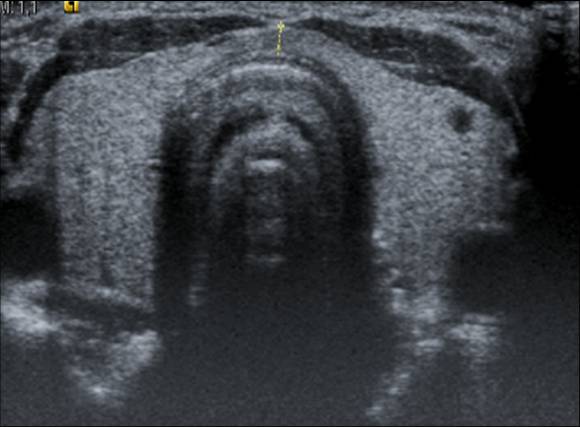

Figura X-9

Figure X-9